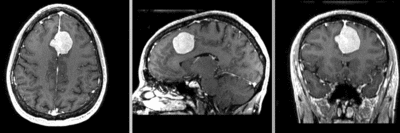

| Fast Affine registration result | ExpertAutomatedRegistration registration result | before/after registration with ExpertAutomatedRegistration module |

- accuracy is the critical criterion here. We need the registration error (residual misalignment) to be smaller than the change we want to measure/detect. Agreement on what constitutes good alignment can therefore vary greatly.

- the two images have strong differences in coil inhomogeneity. This affects less the registration quality but hampers evaluation. Most of the difference does not become apparent until after registration in direct juxtaposition. Bias field correction beforehand is recommended.

- because we seek to assess/quantify regional size change, we must use a rigid (6DOF) scheme, i.e. we must exclude scaling.